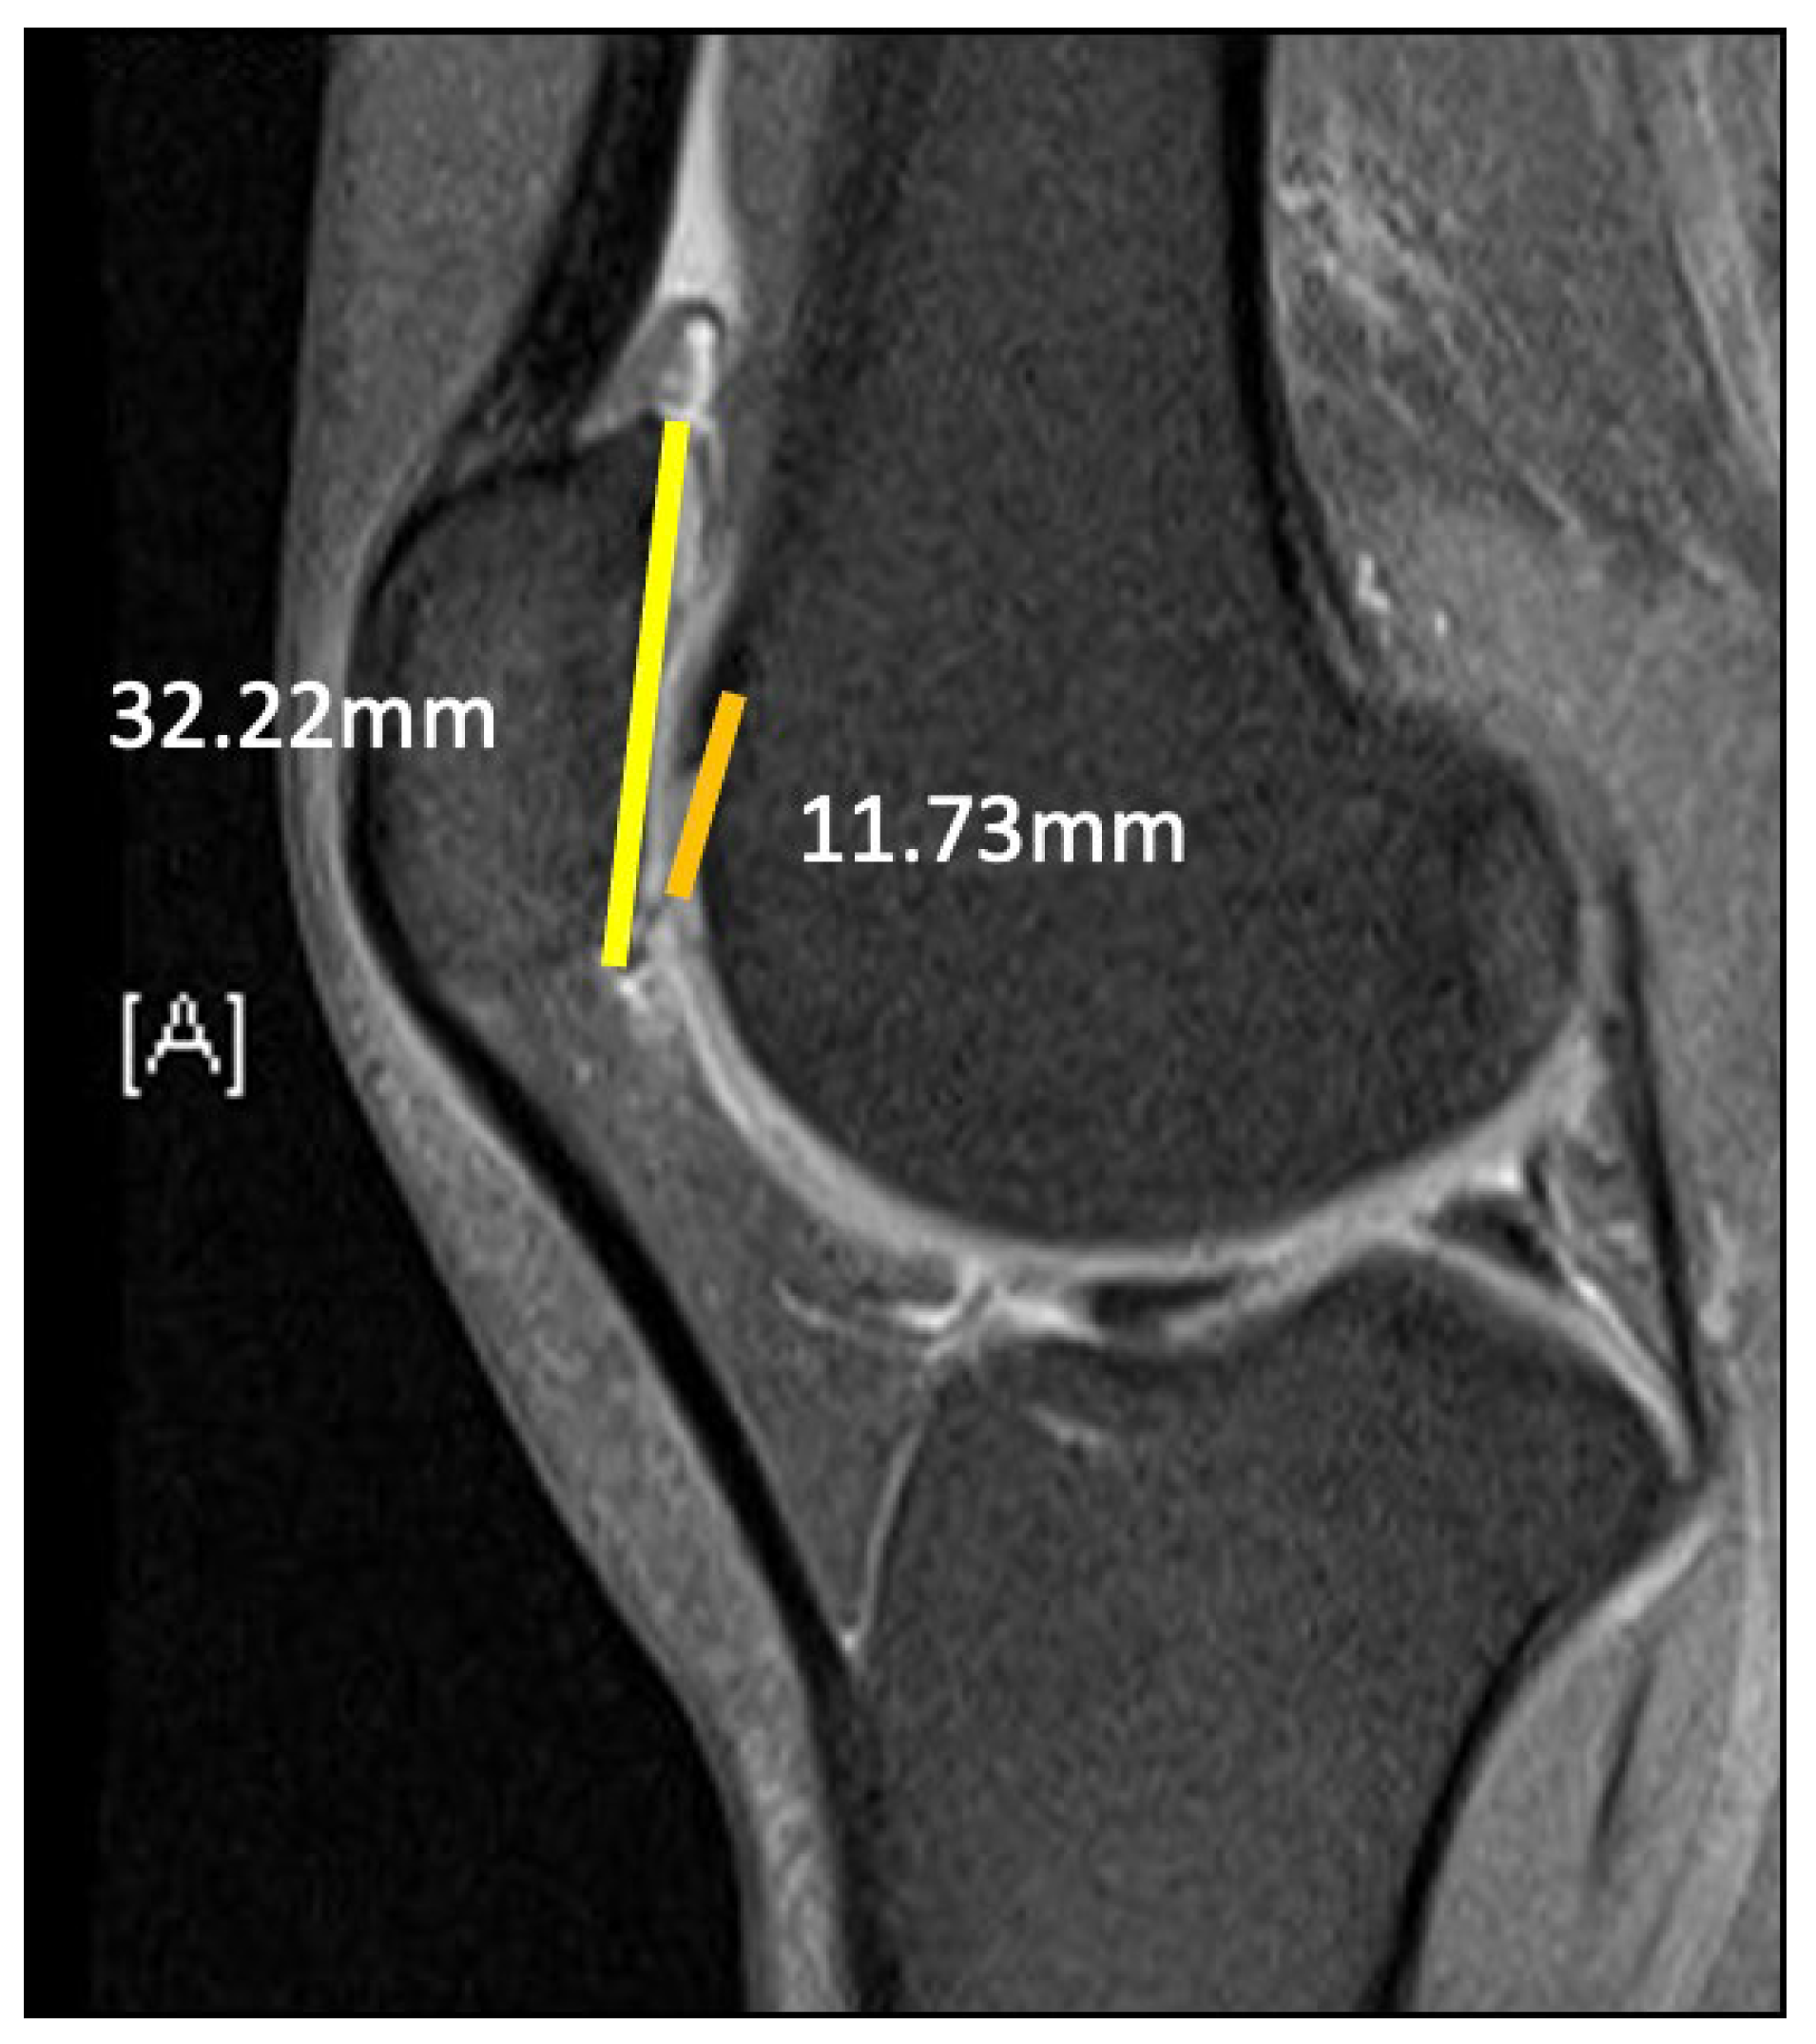

2.1. Case

3.2. Patella Alta